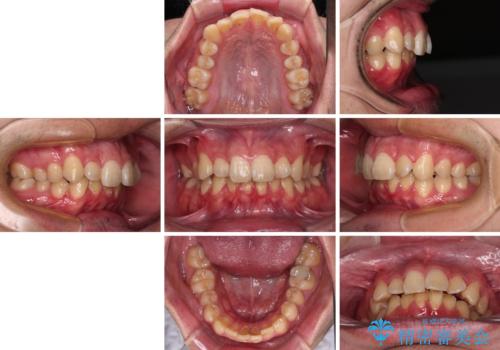

上顎前歯のデコボコを改善してスッキリした口元に ワイヤー装置での非抜歯矯正

- 上顎前歯のデコボコを気にして来院された患者様です。

上下前歯にデコボコがありましたが、特に上顎の叢生が強く、通常に歯列を整えると、上顎が前方に突出し、口元の突出感が残った仕上がりとなる可能性が考えられました。

補助装置を用いて上顎歯列全体を後方に移動させる力をかけ、唇が閉じやすいような仕上がりを目指して、ワイヤー装置にて矯正治療を行うこととしました。

非常に咬合力が強く、左側の臼歯がなかなか後方へ移動できなかったのですが、2年ほどかけて大変満足のいく仕上がりを達成することができました。